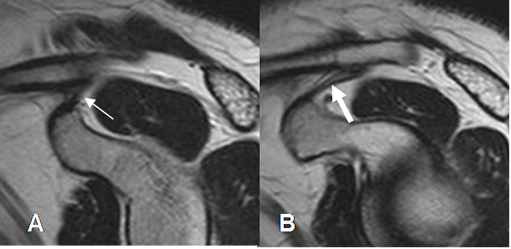

La artroresonancia (ArtroRM) es la mejor técnica para evaluar los ligamentos y el labrum glenoideo. (Fig 23 a 26). La aplicación de la mezcla intra-articular del contraste, puede hacerse mediante guía fluoroscópica o ecográfica. (13). La ecografía se considera la técnica mas fácil, rápida y menos dolorosa. (13). (Fig 22).

Fig 22. Técnica de ArtroRM por ecografía.

A: RM axial en FFE y B: Ecografía vista axial. Abordaje anterior, con trayecto de la aguja en el espacio coracohumeral. Al atravesar el subescapular (Flechas gruesas), se inyecta el contraste.

C: Ecografía axial. Aguja (Flecha delgada) cruzando el músculo subescapular. (Flecha gruesa).